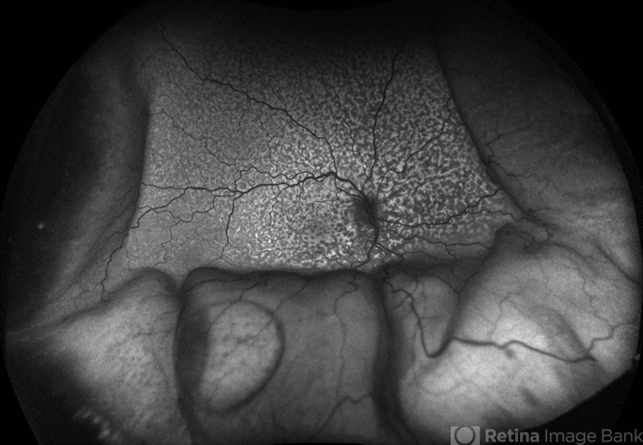

- Choroidal, window defect, exudative detachment, chorioretinitis

- 61 year old male with Idiopathic Uveal Effusion Syndrome with starry night appearance on fluorescein. 3 weeks s/p single external drainage retinotomy and 9 weeks of oral pred with recurrent choroidal effusions. Has since returned to surgery for secondary drainage retinotomy; subretinal fluid remain persistent.